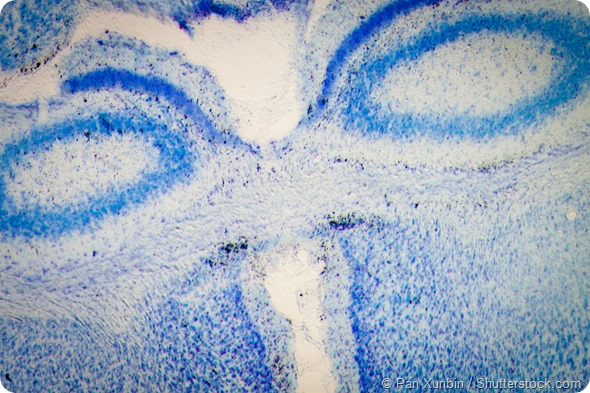

Rat brain hippocampal neurons - microscopy micrograph.